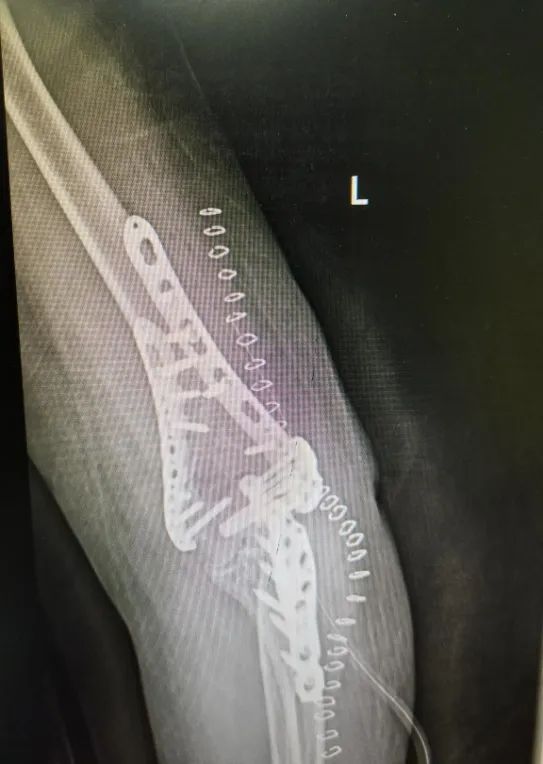

骨折是临床上最常见的疾病,这不,今年1月份的一天,邵女士下楼走台阶时不慎摔倒,伤及左肘,当时感觉疼痛剧烈,立即就诊于北京燕化医院急诊科,查X片提示:左肱骨髁间骨折(闭合性),进一步完善相关检查,一周后顺利接受了手术治疗。

在这种传统观念的影响下,4周过去了,邵女士的胳膊不仅仍肿胀疼痛,而且还屈伸两难,为了早一点恢复,她再次就诊于北京燕化医院康复医学科,经查体:左肘关节及周围组织肿胀明显,左肘关节活动度(-50°)-90°,活动范围明显受限,康复医学科医生和技师给予制定了详细的康复治疗计划,4周后左肘关节活动度达到了(-15°)-100°,胳膊不仅能屈,也能伸了,肿胀疼痛也消失了,还能双手配合做一些家务劳动,邵女士也露出了高兴的笑容,每天都积极的来康复科治疗。